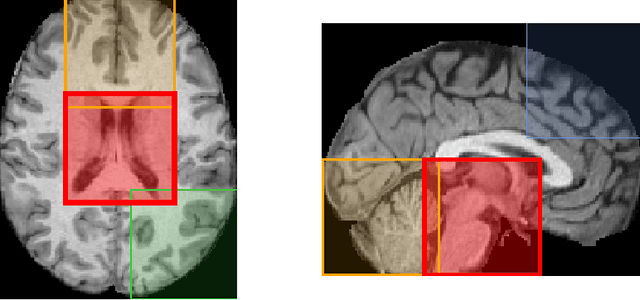

Abstract:Brain age estimation from Magnetic Resonance Images (MRI) derives the difference between a subject's biological brain age and their chronological age. This is a potential biomarker for neurodegeneration, e.g. as part of Alzheimer's disease. Early detection of neurodegeneration manifesting as a higher brain age can potentially facilitate better medical care and planning for affected individuals. Many studies have been proposed for the prediction of chronological age from brain MRI using machine learning and specifically deep learning techniques. Contrary to most studies, which use the whole brain volume, in this study, we develop a new deep learning approach that uses 3D patches of the brain as well as convolutional neural networks (CNNs) to develop a localised brain age estimator. In this way, we can obtain a visualization of the regions that play the most important role for estimating brain age, leading to more anatomically driven and interpretable results, and thus confirming relevant literature which suggests that the ventricles and the hippocampus are the areas that are most informative. In addition, we leverage this knowledge in order to improve the overall performance on the task of age estimation by combining the results of different patches using an ensemble method, such as averaging or linear regression. The network is trained on the UK Biobank dataset and the method achieves state-of-the-art results with a Mean Absolute Error of 2.46 years for purely regional estimates, and 2.13 years for an ensemble of patches before bias correction, while 1.96 years after bias correction.